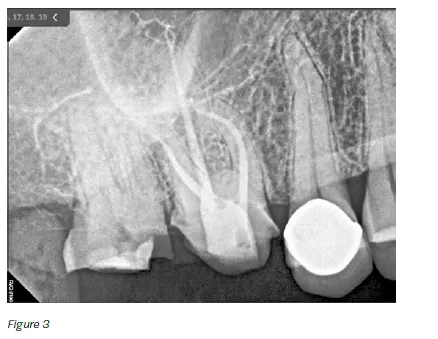

4. The canals were dried before placing ZenSeal™ Bioceramic

Sealer (Figure 3).

5. The canals were obturated using SimpliCore™ for Zen-

Flex™ ONE Primary (Figures 2 and 3).